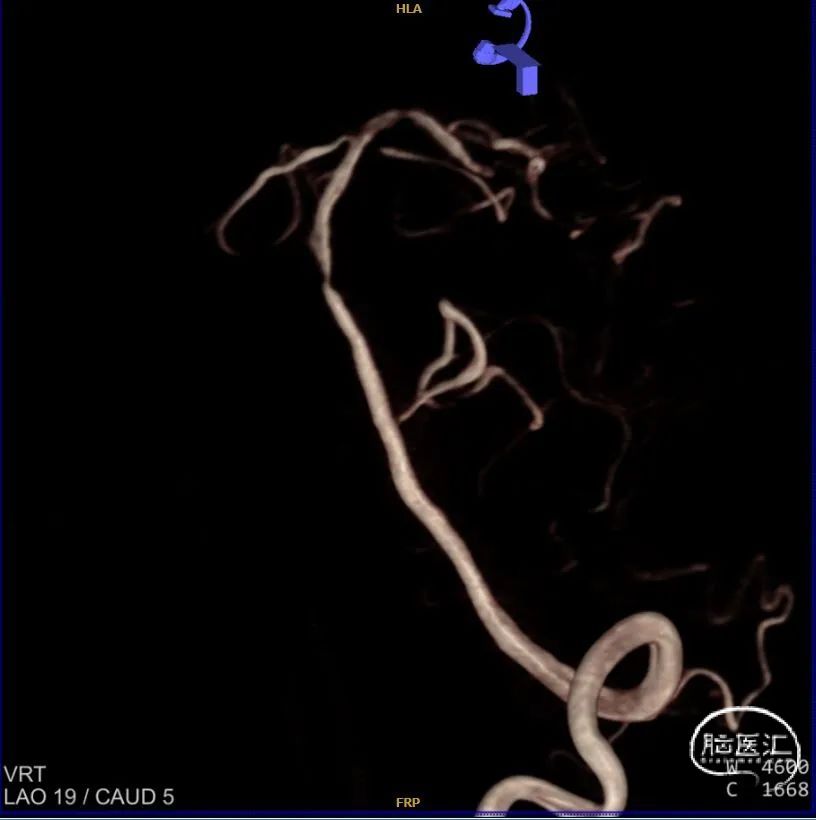

头颈联合CTA提示:左侧椎动脉V4段重度狭窄,右侧椎动脉V2以远闭塞。

左椎正侧位造影提示:LV4重度狭窄。

超选左椎行3D旋转造影。

术后左椎3D旋转造影。